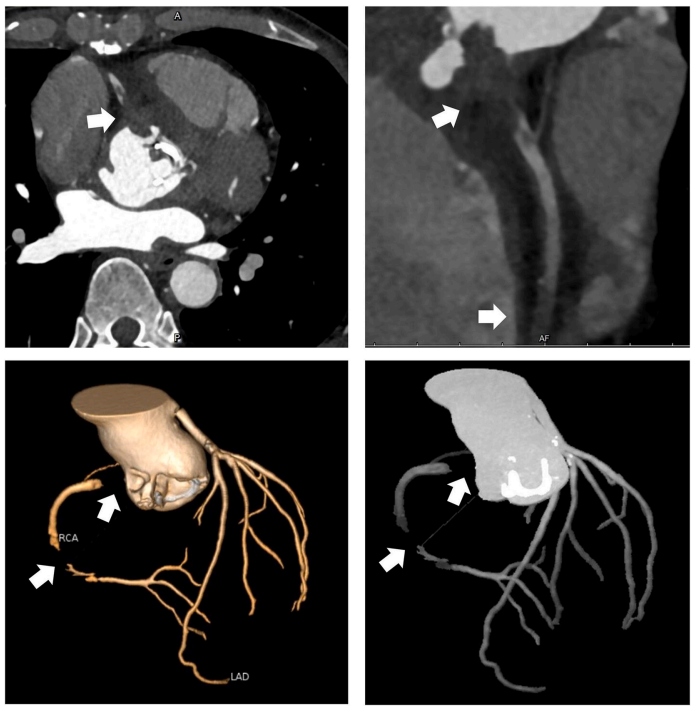

冠脉CT显示右冠窦瓣周脓肿(图2A)伴右冠窦至右心房瘘管形成(图2B)。右冠窦及无冠窦下方有大量脓肿,压迫左心房并侵蚀右纤维三角(图3)。由于赘生物侵袭导致右冠状动脉(RCA)近段慢性闭塞,右冠状动脉中段观察到栓塞碎片(图4)。患者高敏肌钙蛋白(hs-cTn)升高至2090ng/mL符合冠脉栓塞引发的心肌损伤表现,以上共同表明为IE导致的广泛解剖破坏,涉及瓣膜及瓣周结构。

图4